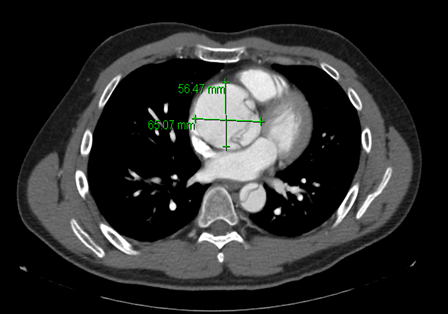

A 45-year-old male presented to a community hospital emergency department with acute neck and chest pain. His pain first started as odynophagia and then extended to his chest and abdomen. He had no history of hypertension, coronary artery disease, diabetes mellitus, or smoking. His family history was significant for a type one aortic dissection in his brother three years earlier at age 55 years and a questionable history of the sudden death of his uncle while he was asleep. Computed tomography angiogram showed an aneurysmal dilation of the aortic root and an acute Stanford type one aortic dissection involving the ascending thoracic aorta, aortic arch, and descending thoracic aorta extending to the abdominal aorta (Figure 1) (Figure 2). His dissection also involved the left brachiocephalic artery extending to the origin of the vertebral artery. Further investigations revealed that his brother had the same type of aortic dissection with extension to his left carotid artery and abdominal aorta, which had been treated with aortic valve replacement and aortoplasty. However, his brother had a history of smoking and diabetes, and his course had been complicated with stroke and right lower extremity compartment syndrome. The patient was transferred for aortoplasty, and after one year follow-up, did not have any complications. He and his brother did not meet any criteria of known connective tissue diseases such as Marfan or Loeys-Dietz syndrome.

Figure 2: Aortic root aneurysm.